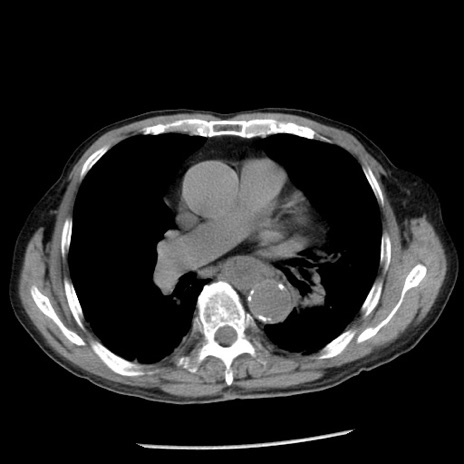

症例26(横断像)

【症例】80歳代男性

【主訴】嘔吐

【現病歴】昨晩2回嘔吐あり、今朝になっても嘔吐あり。来院。

【既往歴】胃潰瘍

【身体所見】意識清明、BT 37.6℃、BP 166/95mmHg、HR 100bpm、SpO2 97%、腹部:平坦・軟、腸蠕動音聴取良好、圧痛なし。

【データ】WBC 21900、CRP 1.46